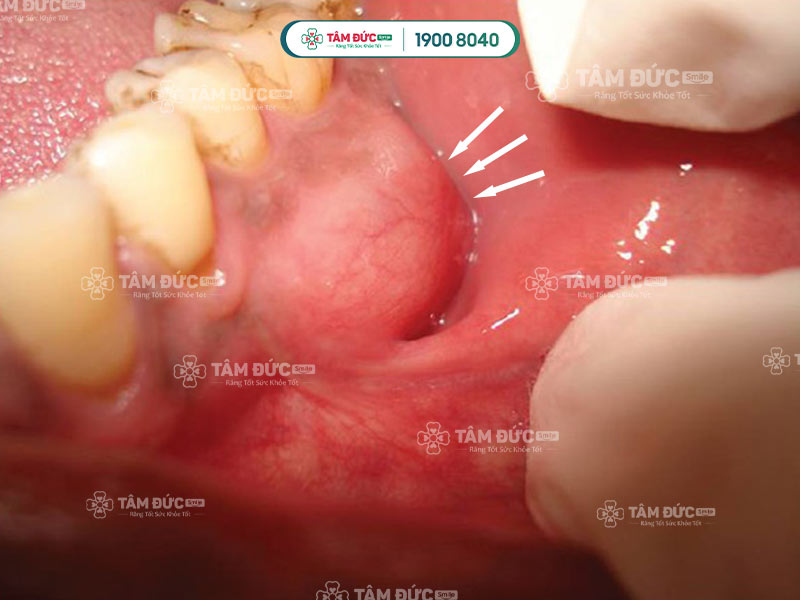

Viêm lợi có mủ do vi khuẩn tấn công vào chân răng

3.2. Viêm lợi có mủ tạo thành khối áp xe chân răng

Áp xe chân răng thường xảy ra khi sâu răng xâm nhập vào tủy mà không được điều trị kịp thời. Đây là tình trạng hình thành ổ mủ tại chân răng, gây đau nhức, sưng hạch cổ, hôi miệng, và sưng mô nướu.